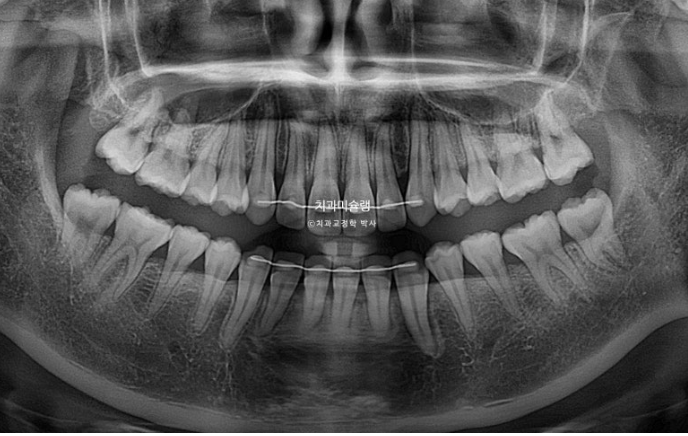

25.11

치아 뿌리 평행도는 좋고 치근흡수는 없습니다.